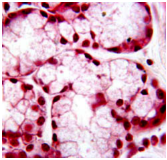

what are A & B and give a reason

A = serous acini

B = mucous acini

- serous acini secrete proteins so they stain strongly with H&E stain.

- mucous acini secrete glycoprotein mucus which stains poorly with H&E.